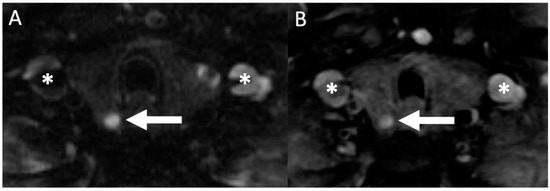

- Sacconi, B.; Argirò, R.; Diacinti, D.; Iannarelli, A.; Bezzi, M.; Cipriani, C.; Pisani, D.; Cipolla, V.; De Felice, C.; Minisola, S.; et al. MR appearance of parathyroid adenomas at 3 T in patients with primary hyperparathyroidism: What radiologists need to know for pre-operative localization. Eur. Radiol. 2015, 26, 664–673. [Google Scholar] [CrossRef]

- Nael, K.; Hur, J.; Bauer, A.; Khan, R.; Sepahdari, A.; Inampudi, R.; Guerrero, M. Dynamic 4D MRI for Characterization of Parathyroid Adenomas: Multiparametric Analysis. Am. J. Neuroradiol. 2015, 36, 2147–2152. [Google Scholar] [CrossRef] [PubMed]

- Argirò, R.; Diacinti, D.; Sacconi, B.; Iannarelli, A.; Diacinti, D.; Cipriani, C.; Pisani, D.; Romagnoli, E.; Biffoni, M.; Di Gioia, C.; et al. Diagnostic accuracy of 3T magnetic resonance imaging in the preoperative localisation of parathyroid adenomas: Comparison with ultrasound and 99mTc-sestamibi scans. Eur. Radiol. 2018, 28, 4900–4908. [Google Scholar] [CrossRef]

- Yildiz, S.; Aralasmak, A.; Yetis, H.; Kilicarslan, R.; Sharifov, R.; Alkan, A.; Toprak, H. MRI findings and utility of DWI in the evaluation of solid parathyroid lesions. La Radiol. Med. 2019, 124, 360–367. [Google Scholar] [CrossRef] [PubMed]

- Ozturk, M.; Polat, A.V.; Celenk, C.; Elmali, M.; Kir, S.; Polat, C. The diagnostic value of 4D MRI at 3T for the localization of parathyroid adenomas. Eur. J. Radiol. 2019, 112, 207–213. [Google Scholar] [CrossRef]

- Memeh, K.O.; Palacios, J.E.; Khan, R.; Guerrero, M.A. Pre-Operative Localization of Parathyroid Adenoma: Performance of 4D Mri Parathyroid Protocol. Endocr. Pr. 2019, 25, 361–365. [Google Scholar] [CrossRef]

- Becker, J.; Patel, V.; Johnson, K.; Guerrero, M.; Klein, R.; Ranvier, G.; Owen, R.; Pawha, P.; Nael, K. 4D–Dynamic Contrast-Enhanced MRI for Preoperative Localization in Patients with Primary Hyperparathyroidism. Am. J. Neuroradiol. 2020, 41, 522–528. [Google Scholar] [CrossRef] [PubMed]